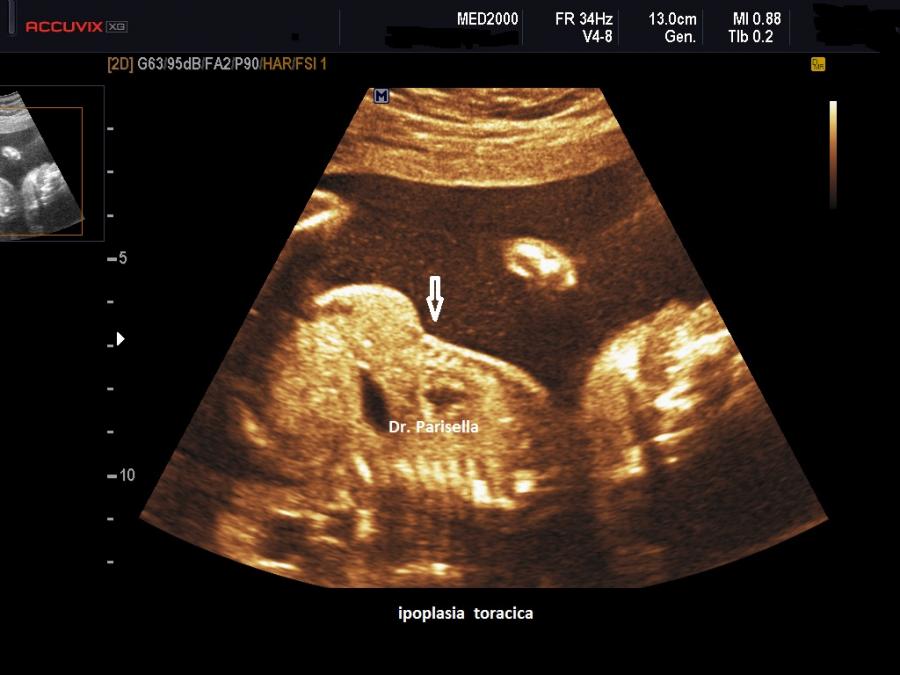

Le SRPS sono un gruppo di displasie scheletriche la cui caratteristica fondamentale è l'ipoplasia toracica. Fanno parte di questo gruppo anche la Distrofia Toracica Asfissiante o Sindrome di Jeune, la Displasia Condroectodermica o Sindrome di Ellis-van-Creveld e la Sindrome Campomelica. Il coinvolgimento del processo displasico delle coste e delle altre ossa della gabbia toracica porta ad una diminuzione delle dimensioni del torace con conseguente ipoplasia polmonare; l'ipoplasia polmonare a sua volta è la principale causa della morte nelle displasie scheletriche letali.

La MICROMELIA SEVERA e l’ IPOPLASIA TORACICA SEVERA (legata al torace stretto con coste corte) sono i segni principali presenti in tutte e quattro i tipi di SRPS e che indirizzano verso una corretta diagnosi. La POLIDATTILIA è presente nei primi due tipi, meno frequentemente nel tipo III, è assente nel tipo IV.

La MICROMELIA SEVERA e l’ IPOPLASIA TORACICA SEVERA (legata al torace stretto con coste corte) sono i segni principali che indirizzano verso una corretta diagnosi.